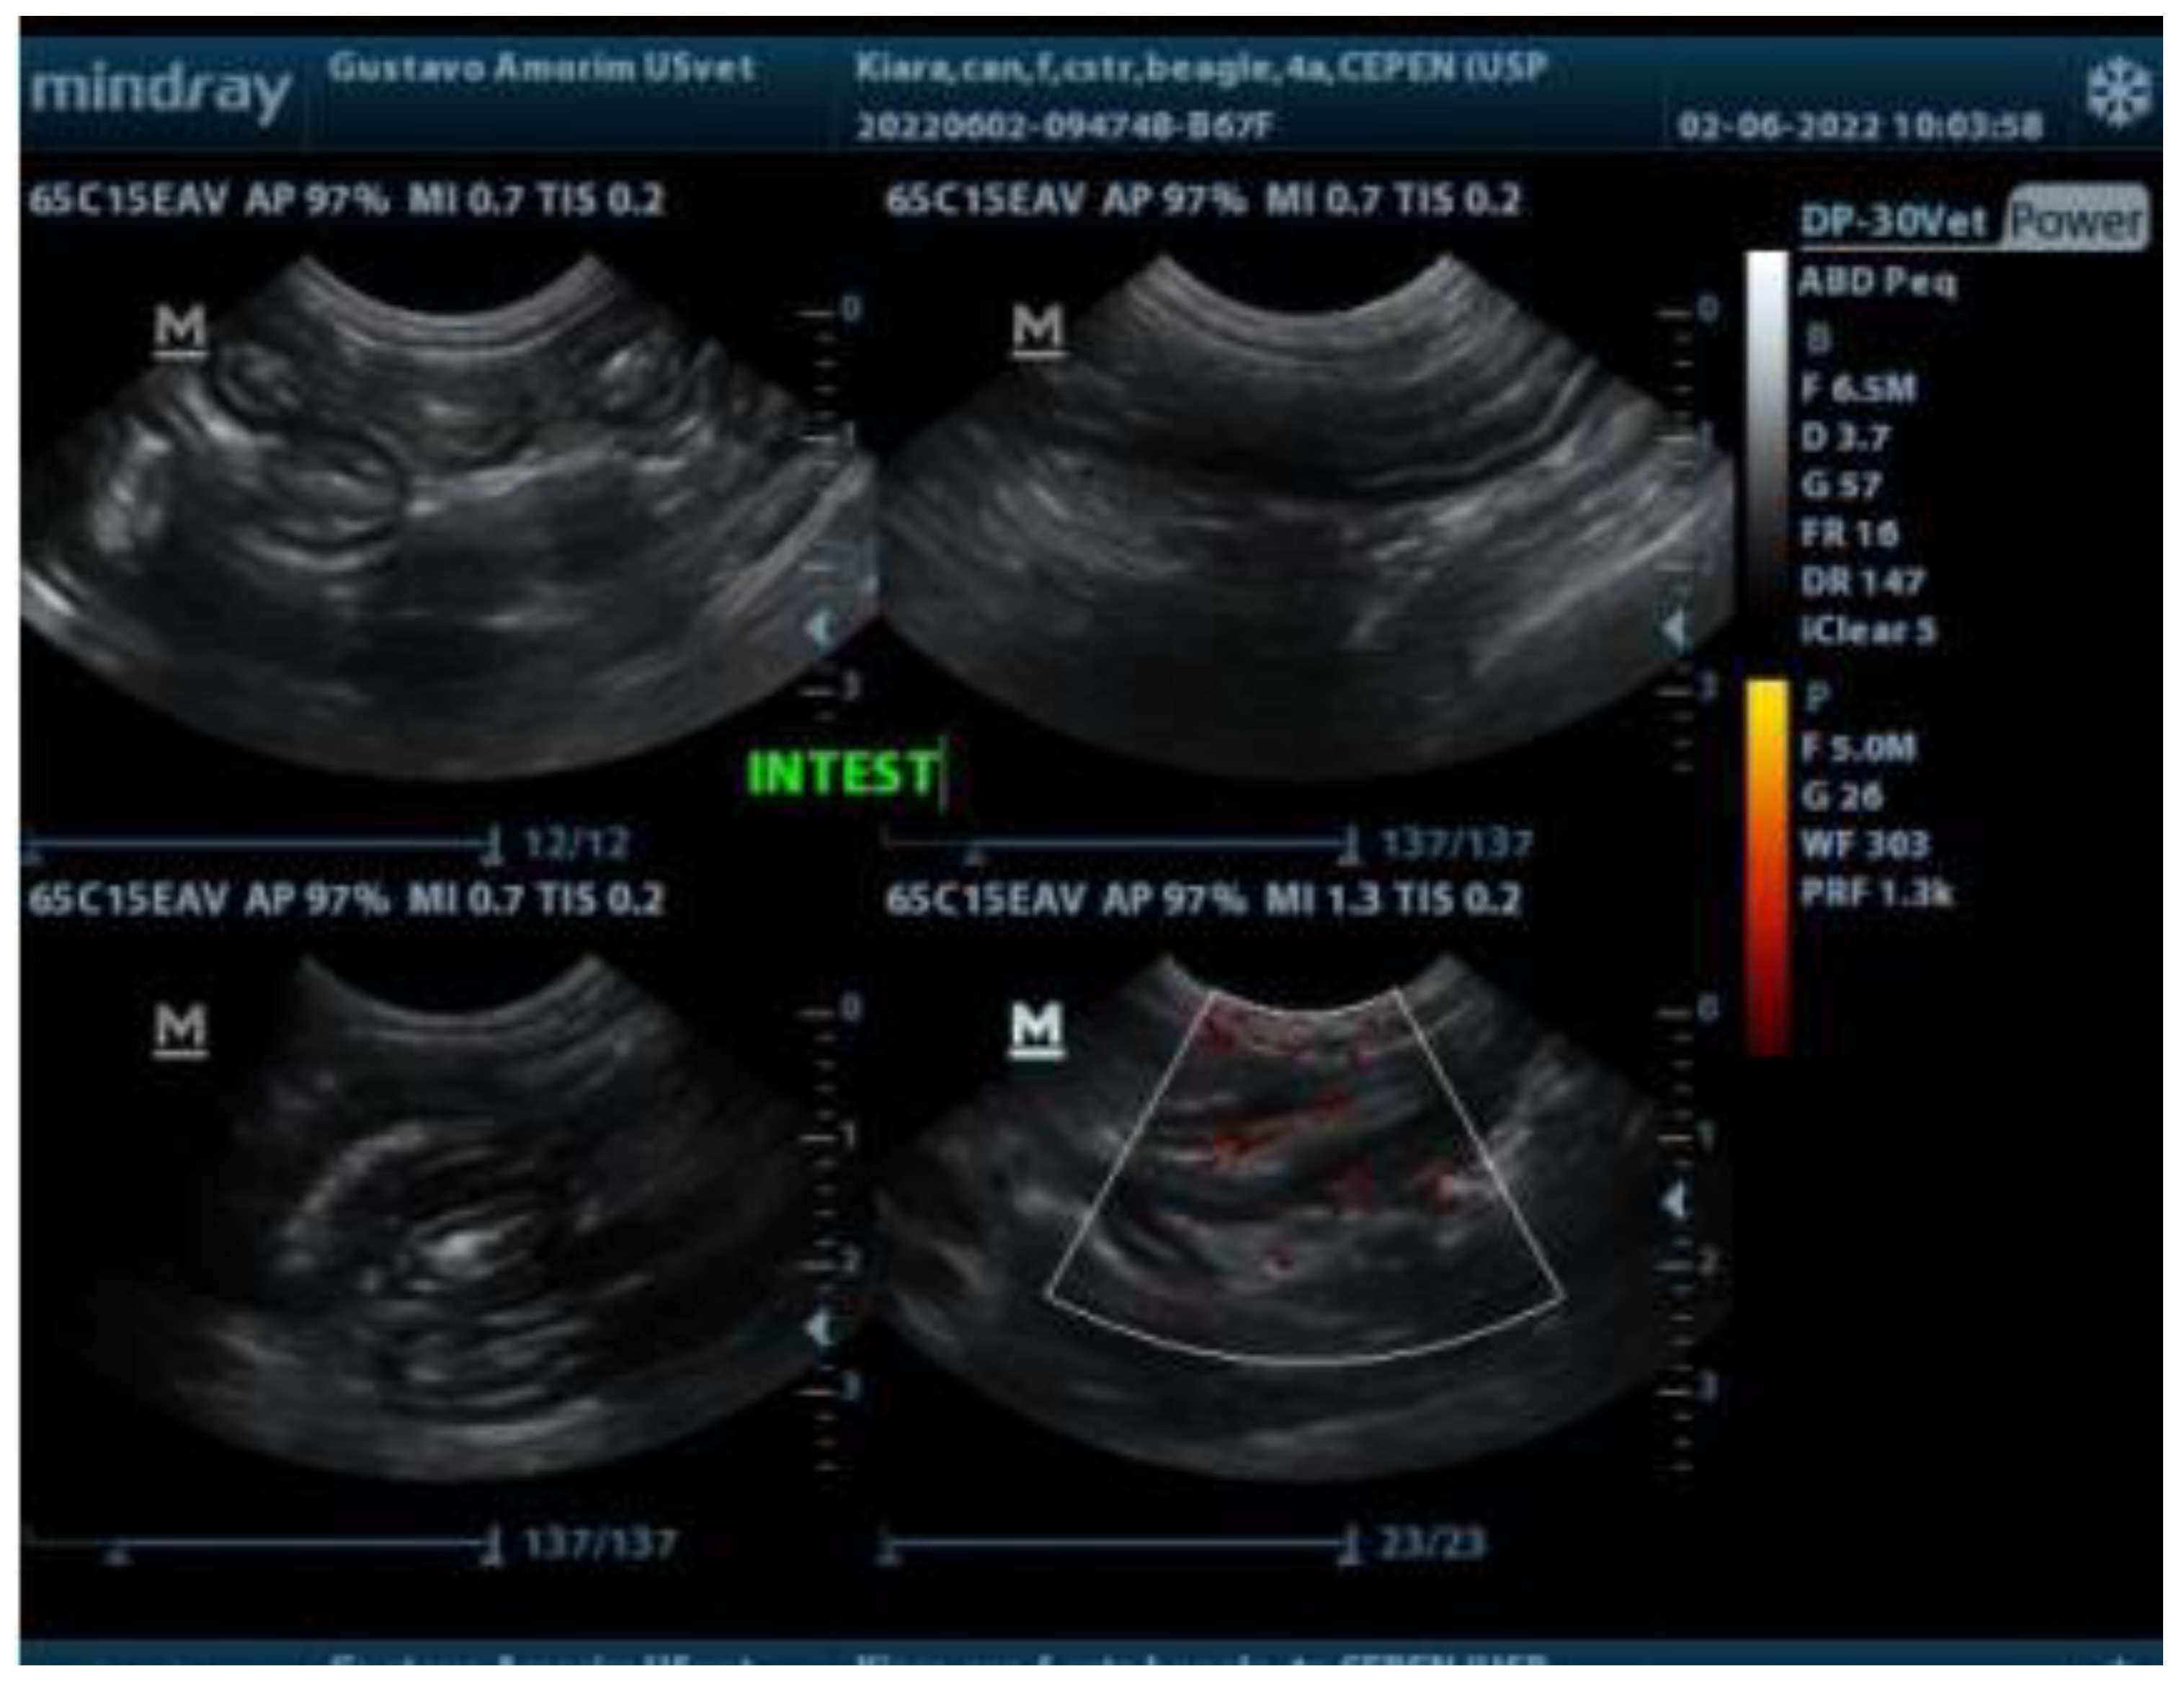

An ultrasonographic examination was conducted to evaluate the gastrointestinal tract after the dog had fasted for 12 hours. In the ultrasonographic images, gas was observed in some regions along the gastrointestinal tract, and diffuse thickening of the muscular layer and generalized increased vascularization were identified (Figure 1). No abnormalities were identified in other systems.

Figure 1.

Ultrasonographic examination of a female beagle dog showing diffuse thickening of the muscular layer and generalized increased vascularization of the intestine.